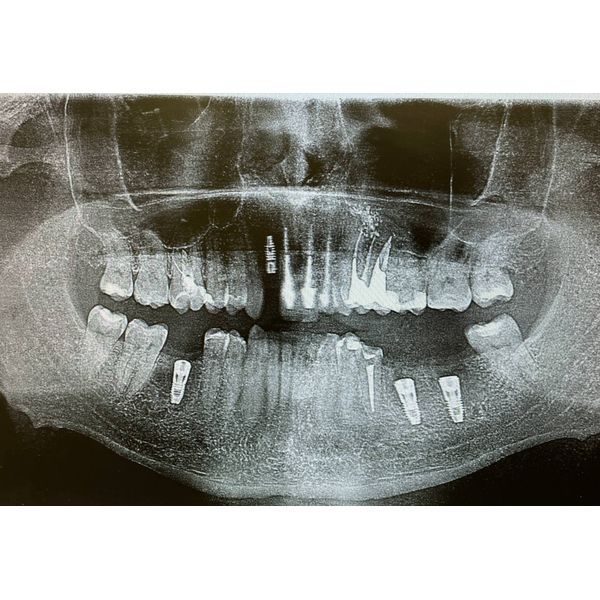

В полости рта определялось обильное количество над- и поддесневых зубных отложений, множественный кариес, дефекты пломб и разрушенные зубы. Отсутствовали два нижних левых моляра и один правый (зубы 3.6, 3.7 и 4.6.). На верхних зубах отмечались несостоятельные коронки.

КТ выявила:

- неудовлетворительную пломбировку корневых каналов некоторых зубов;

- разрушение верхнего резца (зуба 1.2) на уровне цемента корня, при этом костная ткань не разрушена;

- удовлетворительное состояние костной ткани в области отсутствующих зубов 3.6, 3.7 и 4.6.